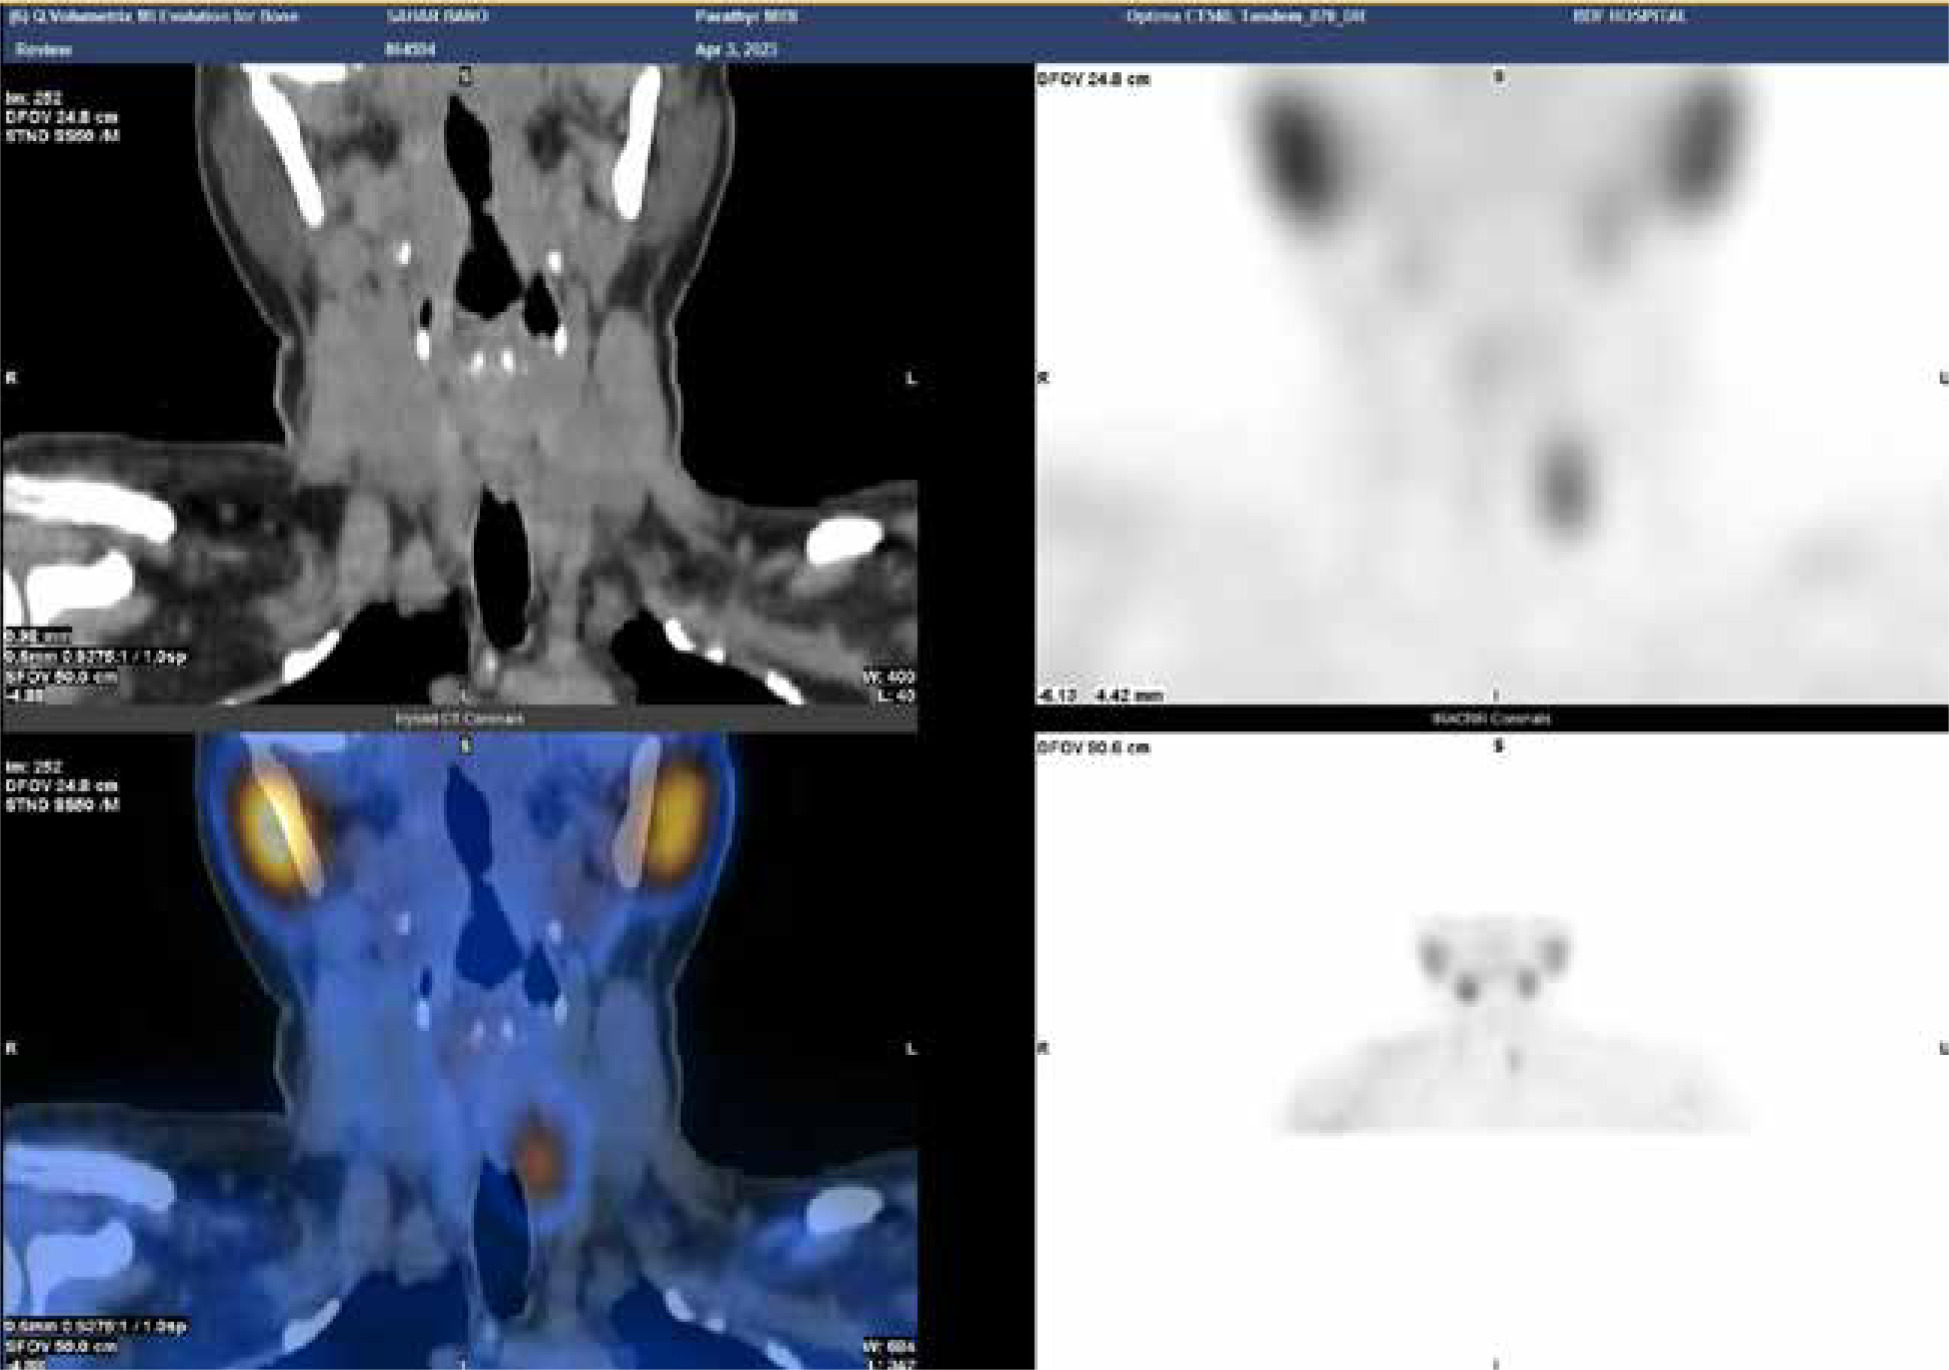

Figure 2

Parathyroid scintigraphy, 99mTC-MIBI showing evidence of persistent hot nodule is seen just inferior to the left thyroid lobe compatible with parathyroid adenoma